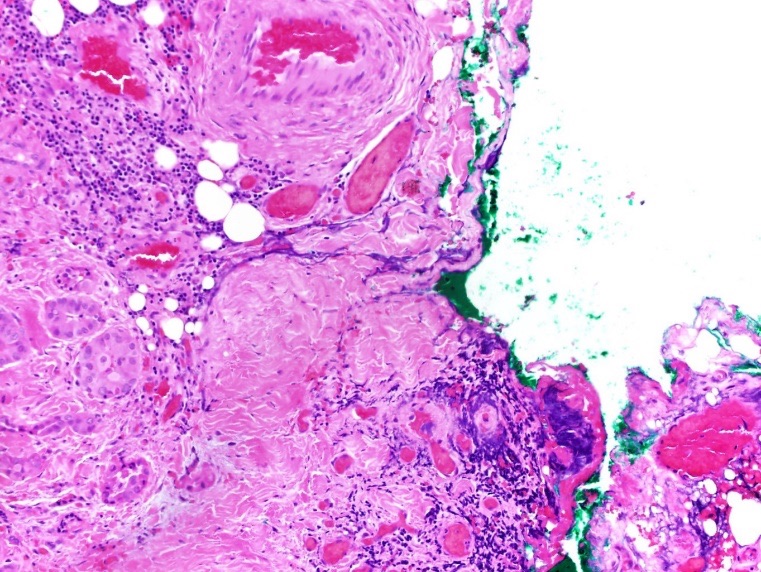

The patient underwent a total thyroidectomy without lymph node dissection. Pathologically, the right thyroid lobe was benign, with no evidence of active malignancy. A 7-mm nodule in the isthmus showed papillary thyroid microcarcinoma with 25% tall-cell morphology and evidence of focal extrathyroidal extension without angioinvasion or lymphatic invasion (Figures 7 and 8).

Figure 7. Hematoxylin-eosin stained pathology of papillary thyroid carcinoma in the isthmus nodule, intermediate-power view (×200) showing tall tumor cells with abundant eosinophilic cytoplasm (aggressive variant of papillary thyroid carcinoma) with focal extrathyroidal extension.